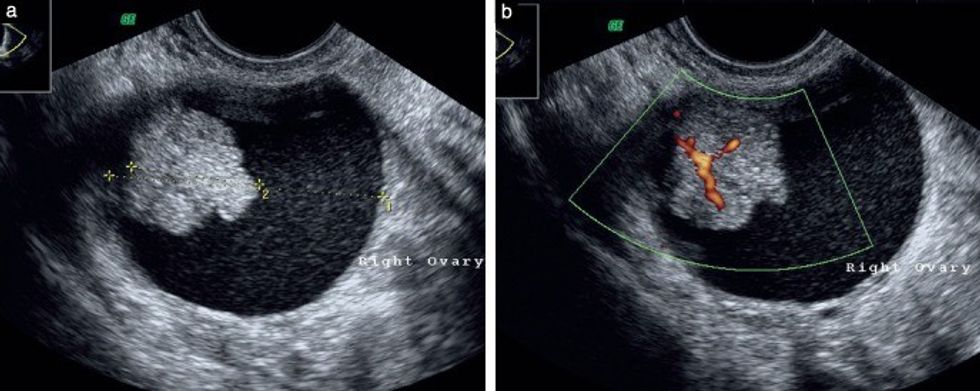

Ekzaminimi klinik gjinekologjik dhe ultrazëri janë metoda standarde në përgjithësi për diagnostikimin e tumoreve të vezoreve. Në ultrazë mund të konstatohet cista e vezores me madhësi të ndryshme deri 30 cm, me areale solide dhe cistike. Një formacion i tillë (tumor) duhet të operohet dhe të largohet komplet vezorja e përfshirë.

Pacientja 61 vjeçe, 3G, 2P, me dhimbje barku tash disa javë. Në ultrazë është vërejtur ciste e vezores së majtë 7 cm në diametër.